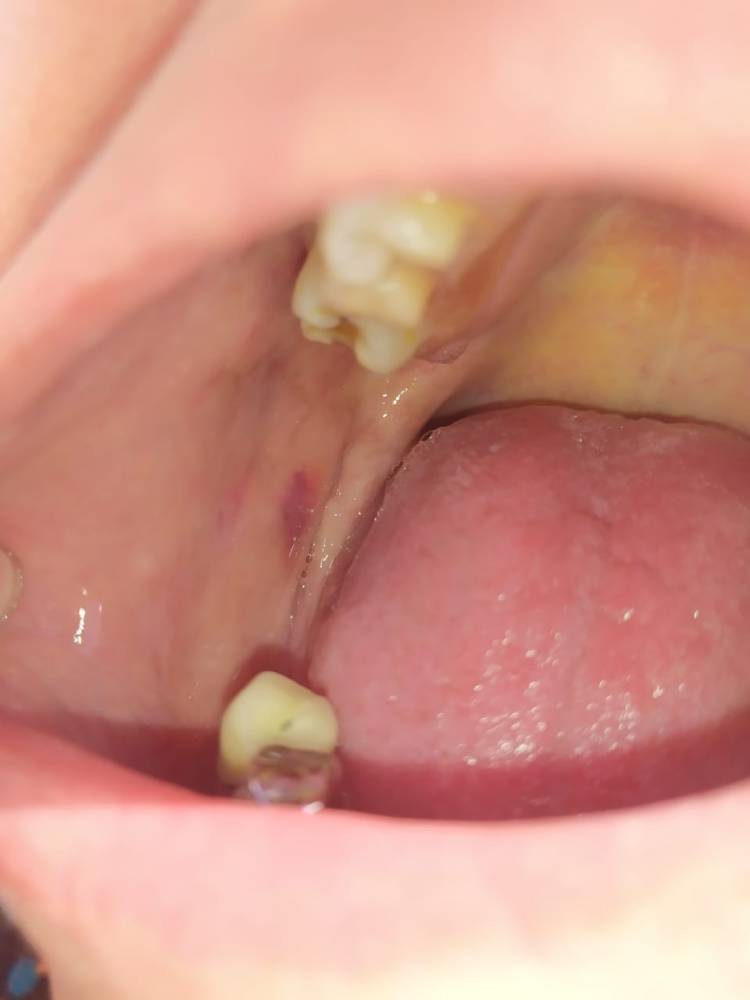

Mácula